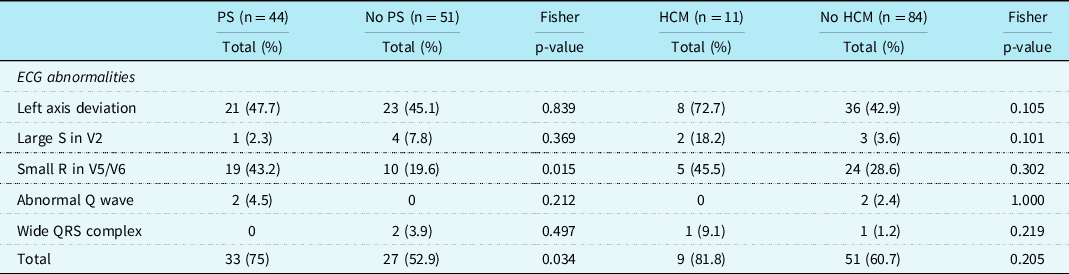

There were 44 (46.3%) patients with left axis deviation, 29 (30.5%) patients with small R-waves in the left precordial leads, and 5 (5.3%) patients with large right precordial S-waves. An abnormal Q-wave was seen in 2 (2.1%) patients and a wide QRS complex also in 2 (2.1%) patients (Table 2). Typical Noonan syndrome-related electrographic features were not more often seen in patients with a mutation in the PTPN11 gene than in patients with other gene mutations. Patients with a mutation in the RAF1 gene had more frequently large S-waves in the right precordial leads (p = 0.002), and patients with SOS1 gene mutation had more frequent wide QRS complexes (p = 0.006).

Patients with pulmonary valve stenosis had more often a small left precordial R-wave than patients without a pulmonary valve stenosis(p = 0.015). No other significant differences were found (Table 4).

Table 4. Specific ECG features in patients with Noonan syndrome with and without pulmonary stenosis and with and without hypertrophic cardiomyopathy

In this cohort, CHD was found in 62.1% and typical Noonan syndrome-related electrocardiographic features in 63.2% of Noonan syndrome patients. The typical Noonan syndrome-related electrocardiographic features were also present in 41.7% of patients without CHD. Left axis deviation was seen in 46.3% of patients, small left precordial R-waves in 30.5%, and large right precordial S-waves in 5.3% of the Noonan syndrome patients. There was no significant difference in the frequency of the individual- specific Noonan syndrome-related electrocardiographic features between the group with CHD and the group without CHD.

A part of the specific Noonan syndrome-related electrocardiographic features may be due to the CHD diagnosed. In patients with pulmonary valve stenosis, the baseline electrocardiogram is often normal in cases of mild pulmonary valve stenosis, and in cases with more severe pulmonary valve stenosis, there may be a slight right axis deviation or signs of right ventricular hypertrophy. However, there was no difference between patients with and without pulmonary valve stenosis regarding the specific Noonan syndrome-related electrocardiographic abnormalities (including left axis), except that patients with pulmonary valve stenosis had more often a small R-wave left precordial, which cannot be explained electrophysiologically by the pulmonary valve stenosis. An abnormal electrocardiogram is common in patients with hypertrophic cardiomyopathy. In literature, most often, abnormal repolarization and Q-waves are reported, and/or left axis deviation. Reference Savage, Seides and Clark34,Reference Helmy, Maauof and Shaaban35 However, in our study, left axis deviation or abnormal Q-waves occurred not more often in patients with hypertrophic cardiomyopathy than in patients without hypertrophic cardiomyopathy. We have the experience that the characteristic features (left axis, small R-wave left precordial), do not change in life or after intervention (surgical intervention, trametinib), however, may be somewhat less accentuated (data are not shown).